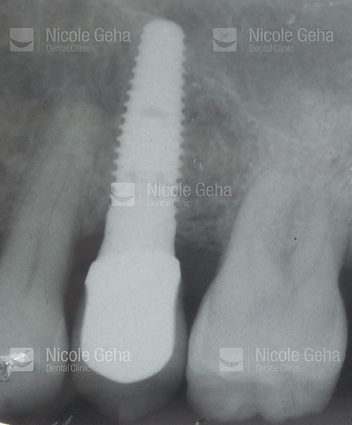

SINGLE IMPLANT

case 1: before

X-RAY After